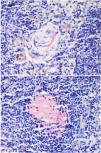

A biopsy taken from these nodes was also reported as amyloidosis, with no evidence of monoclonality. Results showed positivity for CD138, Kappa, Lambda, Congo red, and IgG4, with negativity for HHV8.

Positive staining was noted for AA amyloid, IgG, and IgG4, particularly in plasma cells. An initial diagnosis of lymphoplasmacytic lymphoma was considered, and excisional biopsies of lymph nodes were planned. The excisional biopsy of the left axillary lymph node was reported as amyloidosis, leading to a referral to the rheumatology department to investigate secondary causes of amyloidosis. IgG subclasses were tested, revealing an IgG4 level of 700 mg/dL. The patient was started on corticosteroid therapy at a dose of 1 mg/kg.

ConclusionIgG4-related disease is a fibro-inflammatory condition that can affect any organ simultaneously or at different times. It is a systemic disease that can involve all organs and often presents with organomegaly, mimicking malignancy. The immunopathogenesis of the disease is not yet fully understood. The most critical step in diagnosis is the histopathological evaluation of the affected organ. Histopathological features distinguishing the disease include dense lymphoplasmacytic infiltrates with predominance of IgG4-positive plasma cells, storiform fibrosis, and obliterative phlebitis.